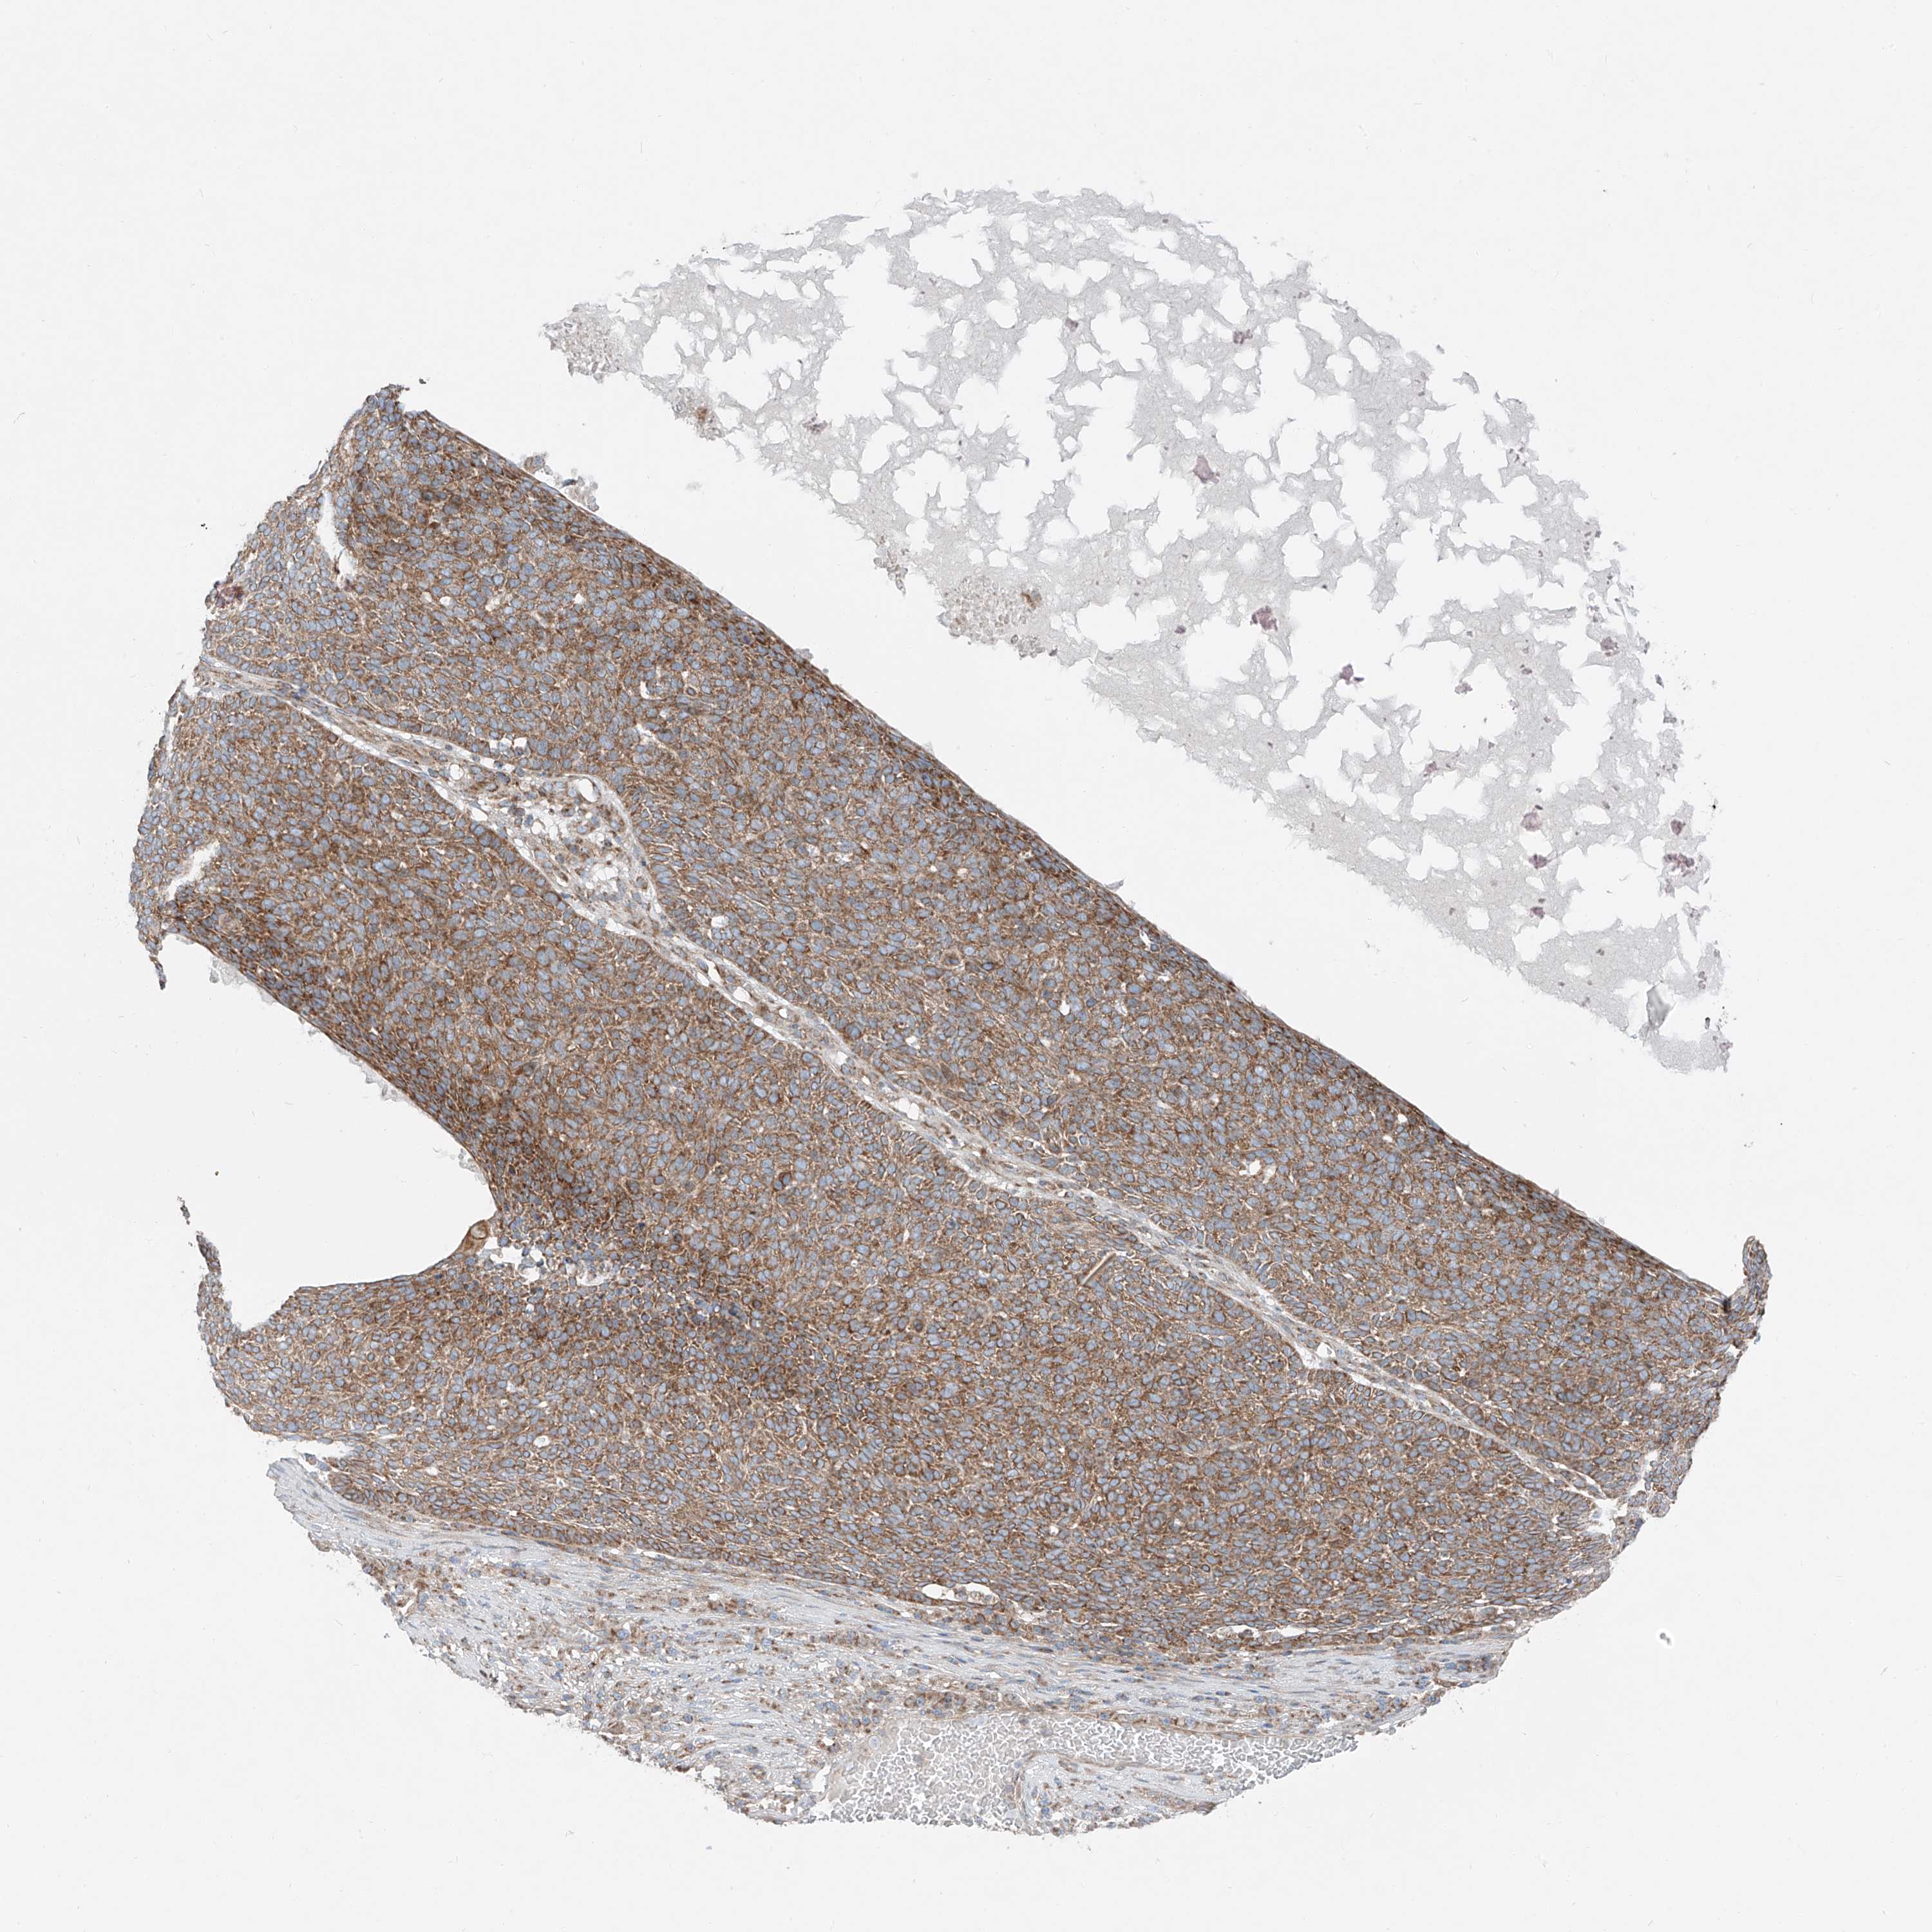

SKIN CANCER - Protein expressioni

A mouse-over function shows sample information and annotation data. Click on an image to view it in a full screen mode. Samples can be filtered based on level of antibody staining by selecting one or several of the following categories: high, medium, low and not detected. The assay and annotation is described here.

Antibody stainingi

Antibody staining in the annotated cell types in the current human tissue is reported as not detected, low, medium, or high, based on conventional immunohistochemistry profiling in selected tissues. This score is based on the combination of the staining intensity and fraction of stained cells.

Each image is clickable and will lead to virtual microscopy that enables deeper exploration of all samples and also displays staining intensity scores, fraction scores and subcellular localization as well as patient and tissue information for each sample.

Antibody HPA030316

Staining

High

Medium

Low

Not detected

Intensity

Strong

Moderate

Weak

Negative

Quantity

>75%

75%-25%

<25%

None

Location

Nuclear

Cytoplasmic/membranous

Cytoplasmic/membranous,nuclear

Squamous cell carcinoma, metastatic, NOS

Squamous cell carcinoma, NOS